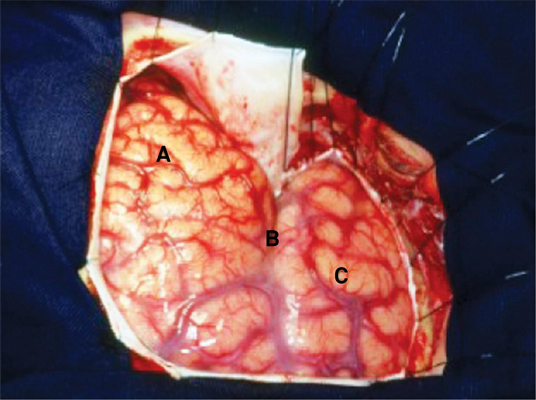

顱內血腫圖片

硬膜下血腫 (7)